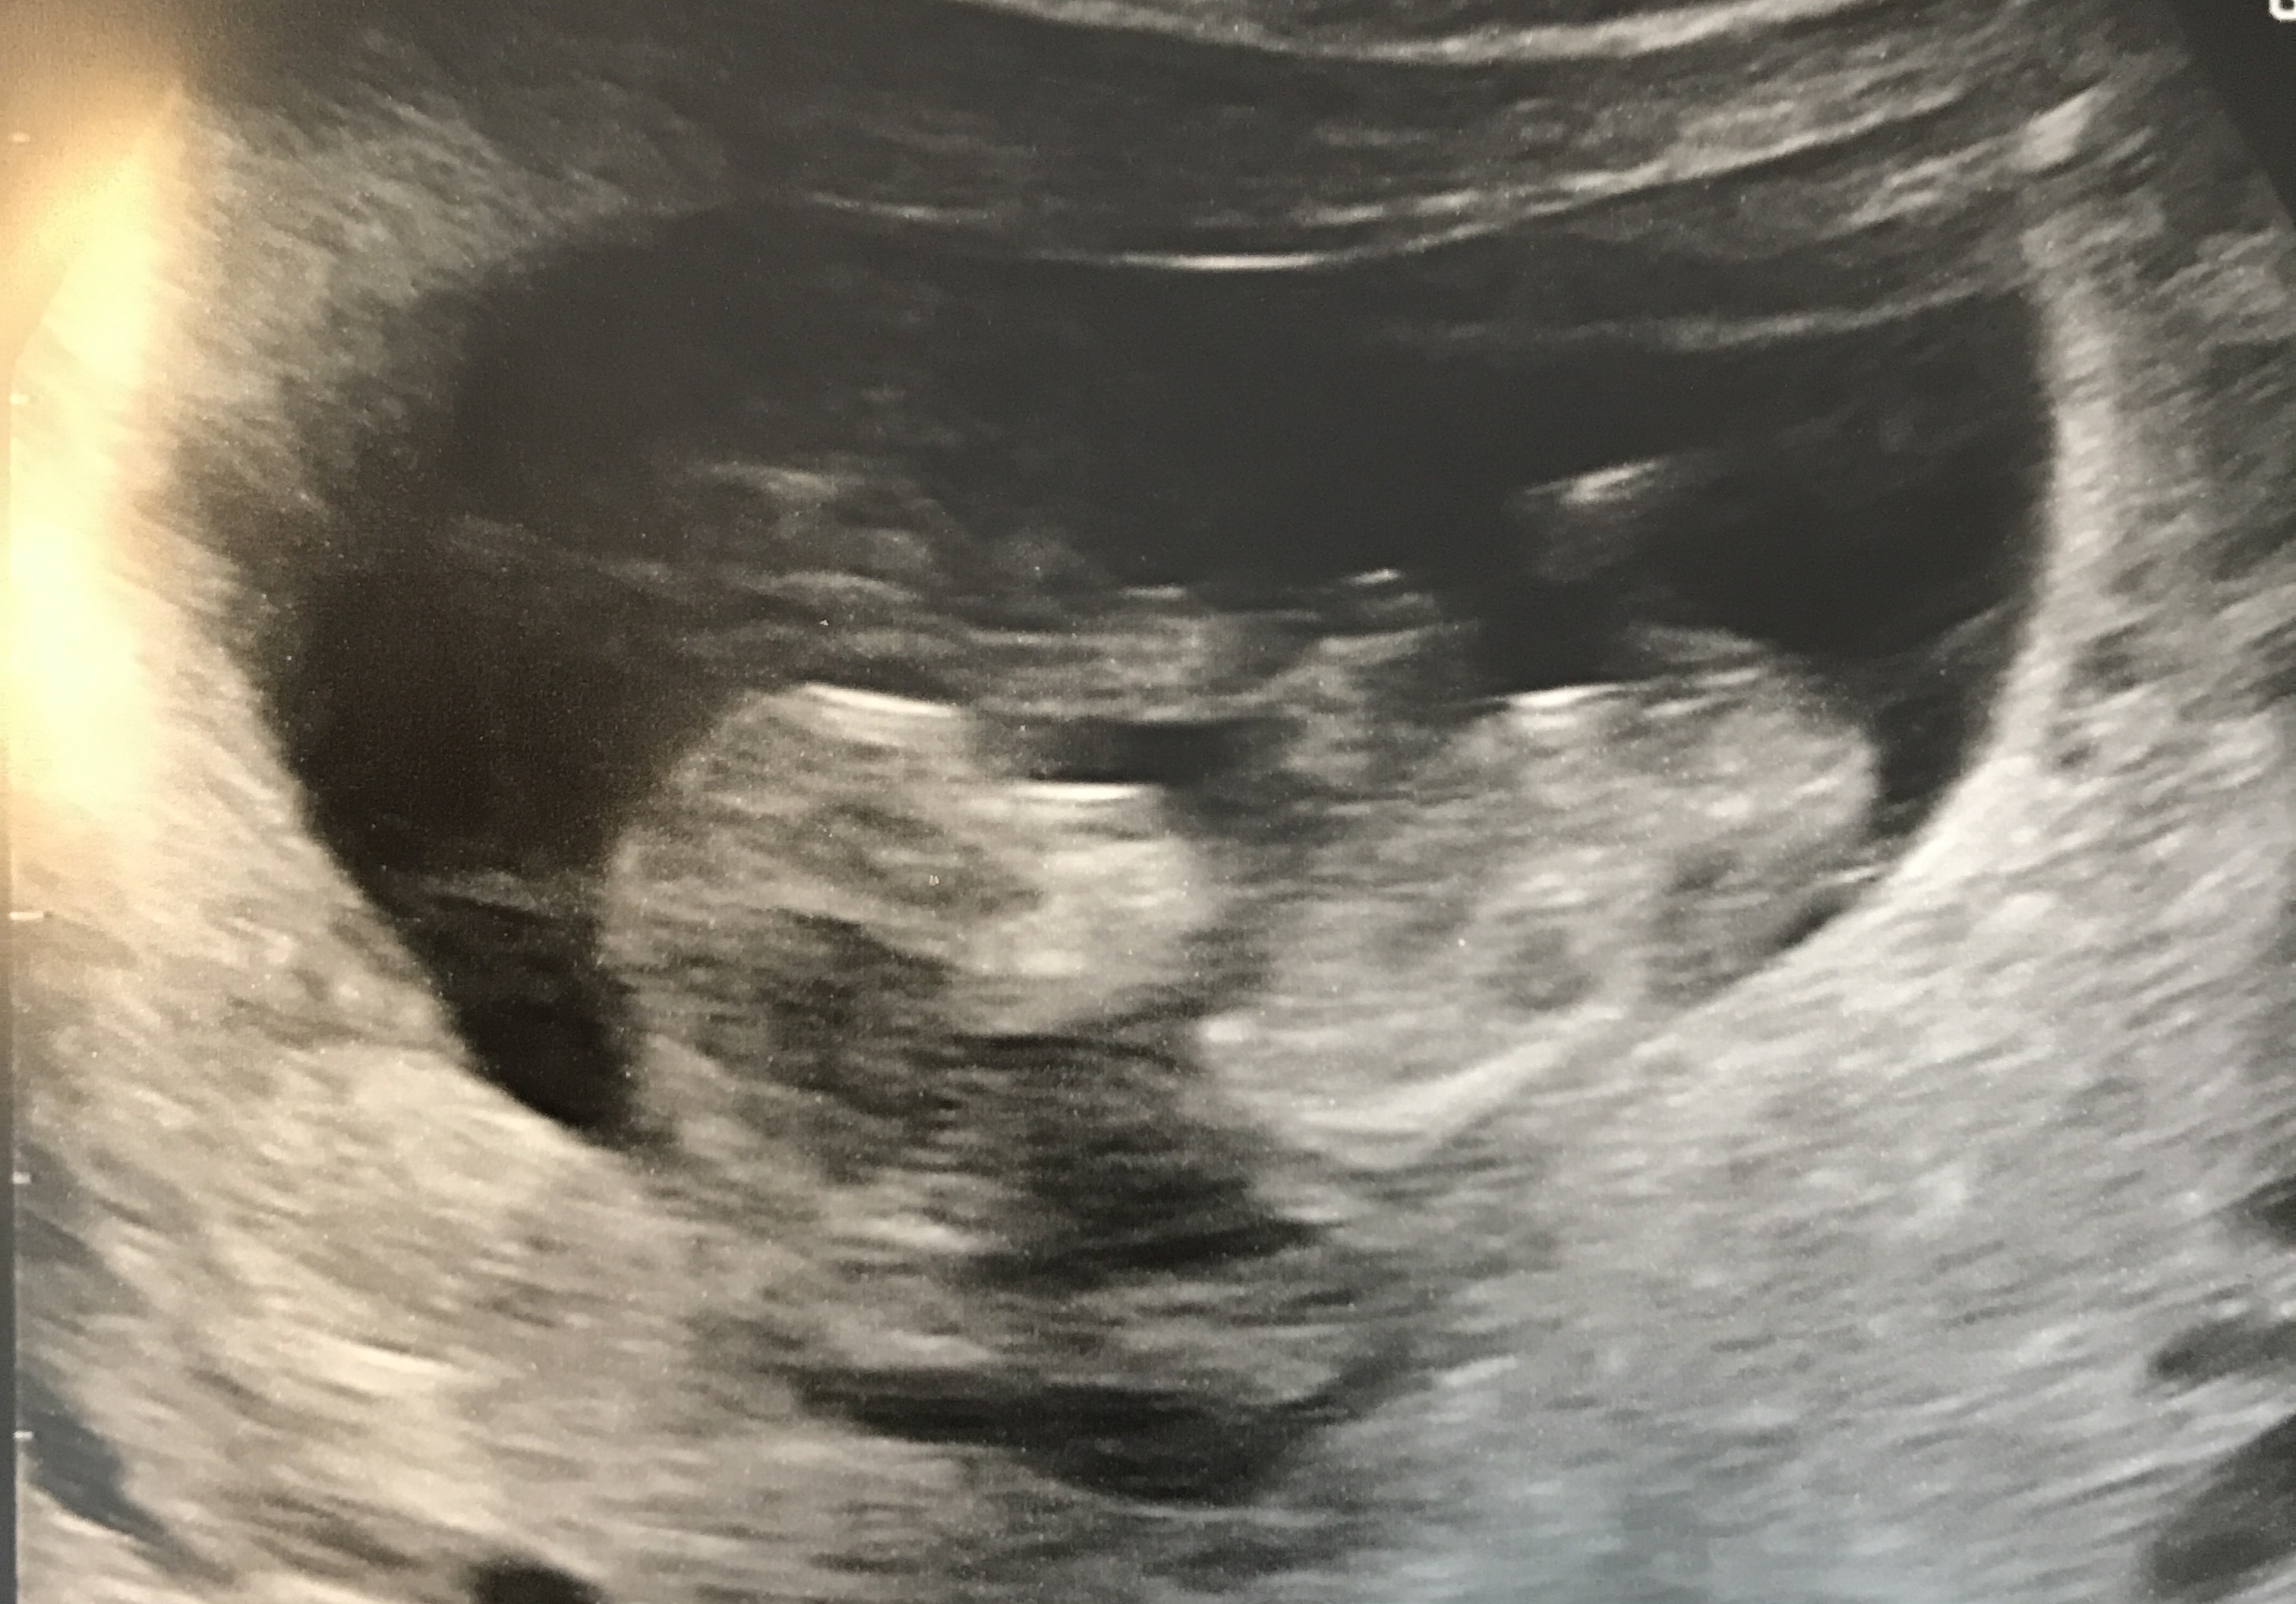

Attachment 36302

Attachment 36303

Hi everyone,

I just got my 13.3 week scan Hope to hear some guesses

Are these photos of a screen? do you happen to have a video you could post for us:) I am unable to zoom your current pictures at all so cannot make any guess atm.

No I don't have a video. When I zoom the pic in I can't upload them anymore. I will try it again